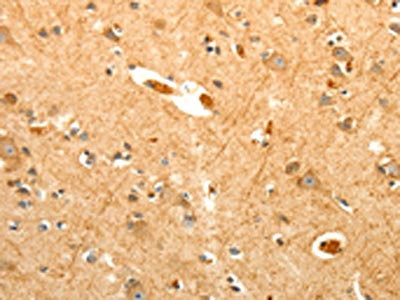

The image on the left is immunohistochemistry of paraffin-embedded Human brain tissue using CSB-PA150036(PTPN6 Antibody) at dilution 1/40, on the right is treated with fusion protein. (Original magnification: ×200)